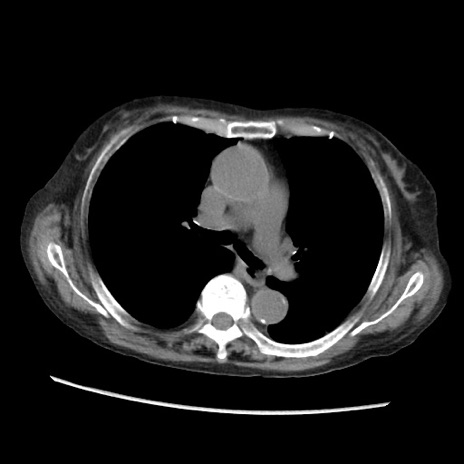

症例31(横断像)

【症例】80歳代 女性

【主訴】腹部膨満感

【現病歴】他院にて肝硬変にてフォロー中。1週間前から便秘、腹部膨満感、臍部腫瘤あり受診となる。

【既往歴】肝硬変

【身体所見】腹部膨隆あり、皮膚変化なし、疼痛なし。

【データ】WBC 4600、CRP 0.25